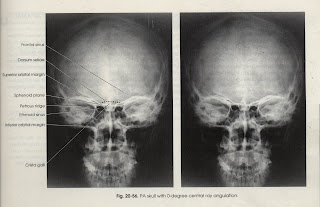

a. AP

Tujuan : Memperlihatkan Os Occypital, Fossa Temporalis, Sinus Frontalis,

Sinus Maxilaris, Cacum Orbita (R dan L) dan OS Petrosum (R dan L)

PP : Pasien erect PA atau supine diatas meja pemeriksaan. Pusatkan MSP

tubuh ditengah garis meja. Elbow Joint flexio dan tempatkan kedua

lengan dalam keadaan nyaman. Bahu diatur sama tinggi pada bidang

PO : Tempatkan kepala diatas kaset dalam keadaan true AP dengan MSP

Kepala tegak lurus bidang film. Kepala flexio sehingga Orbito Meatal Line tegak lurus bidang film. Gunakan grid

CR : Tegak lurus bidang film

CP : Pada Glabella